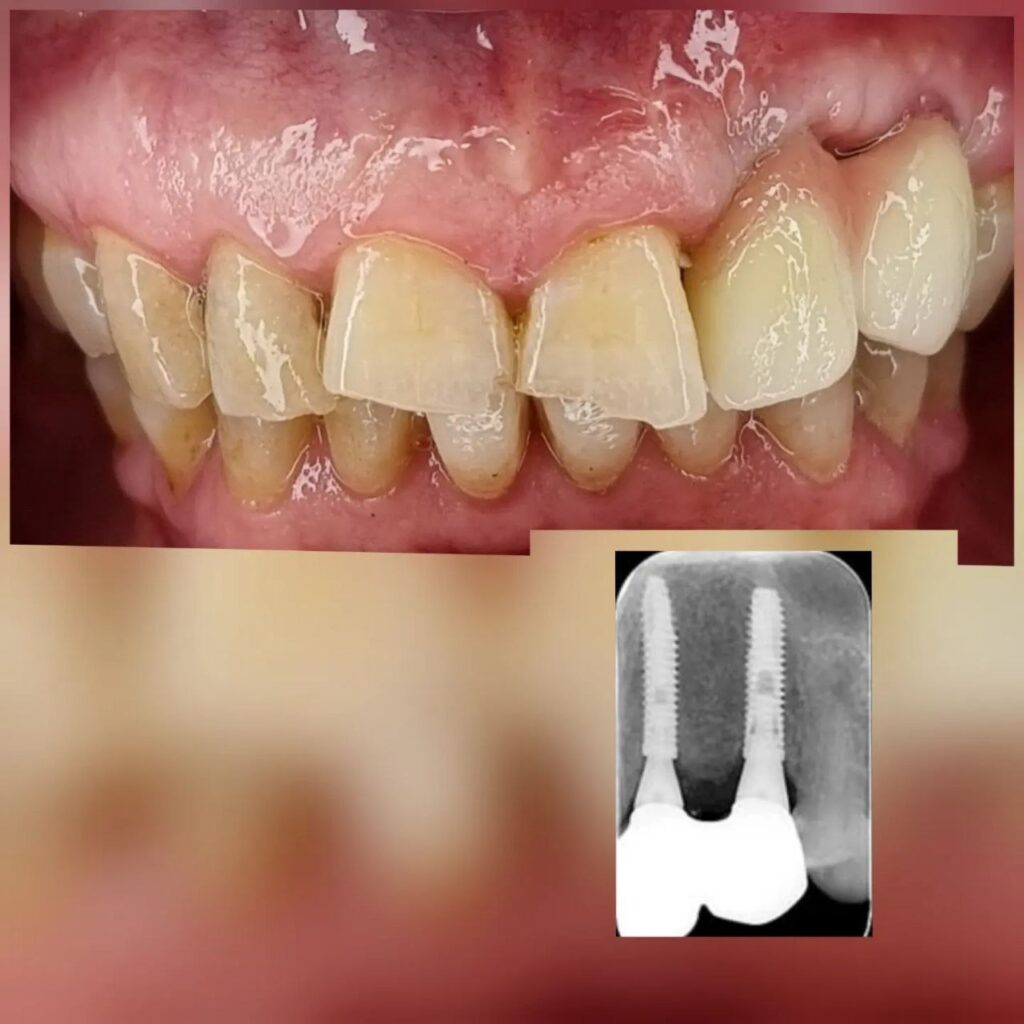

کاشت ایمپلنت دندان

اطمینان حاصل کردن از اینکه دندانهایتان به نحوی زیبا و طبیعی جایگزین شدهاند، از اهمیت بسیاری برخوردار است. ایمپلنت دندان به عنوان یک روش درمانی دائمی در دندانپزشکی شناخته میشود که حاصل آن، یک دندان زیبا و طبیعی در دهان شما خواهد بود.

هرچند که این روش درمانی هزینهی بیشتری نسبت به روشهای دیگر دارد، اما ارزش زیبایی که ایجاد میکند، قابل انکار نیست. ایمپلنتها به قدری شبیه به دندانهای طبیعی هستند که به سختی میتوان آنها را از دیگر دندانها تشخیص داد.